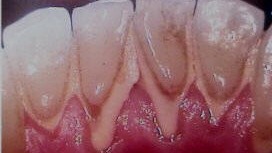

Coral Dental whose other name is calculus dirt in the mouth is attached to the teeth for long periods so that over time will harden and petrified that it is difficult to brush my teeth cleaned. In terms of appearance tartar is less eye-catching, so for those concerned about the appearance should be cleaned with a fine and true.

Everyone in the disparate menghasilang tartar in the mouth. There are easily formed and there is also a long time depending on environmental conditions in the formation of the mouth, the content in the saliva (spit), the food we eat, the condition of the teeth, the type of bacteria that exist in our mouths, and others.